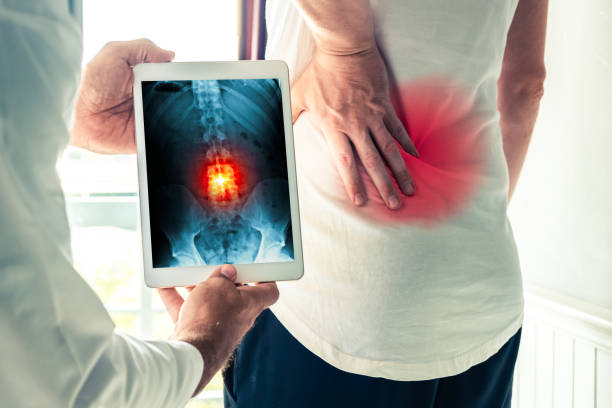

Dr. Yasmeh specializes in motion-preserving spine procedures — including cervical laminoplasty, artificial disc replacement, microdiscectomy, and robotic-assisted minimally invasive surgery. Every procedure starts with a careful conversation about whether surgery is truly the best path.

- Minimally invasive techniques — small incisions, less tissue damage, faster recovery.

- Motion-preserving — cervical laminoplasty and artificial disc replacement instead of routine fusion.

- Minimally invasive spine surgery (MISS) uses smaller incisions and specialized retractors and instruments to access the spine while sparing muscle and other surrounding tissues. For most patients, that translates into less pain, less blood loss, shorter hospital stays, and faster return to normal activities.

- Yes. Laminoplasty preserves motion at the operated levels by reshaping the back of the vertebrae to create more space for the spinal cord — without joining the bones together. Fusion is sometimes still the right choice, but it permanently eliminates motion at the fused levels. Dr. Yasmeh is among a small percentage of surgeons specifically trained in laminoplasty.